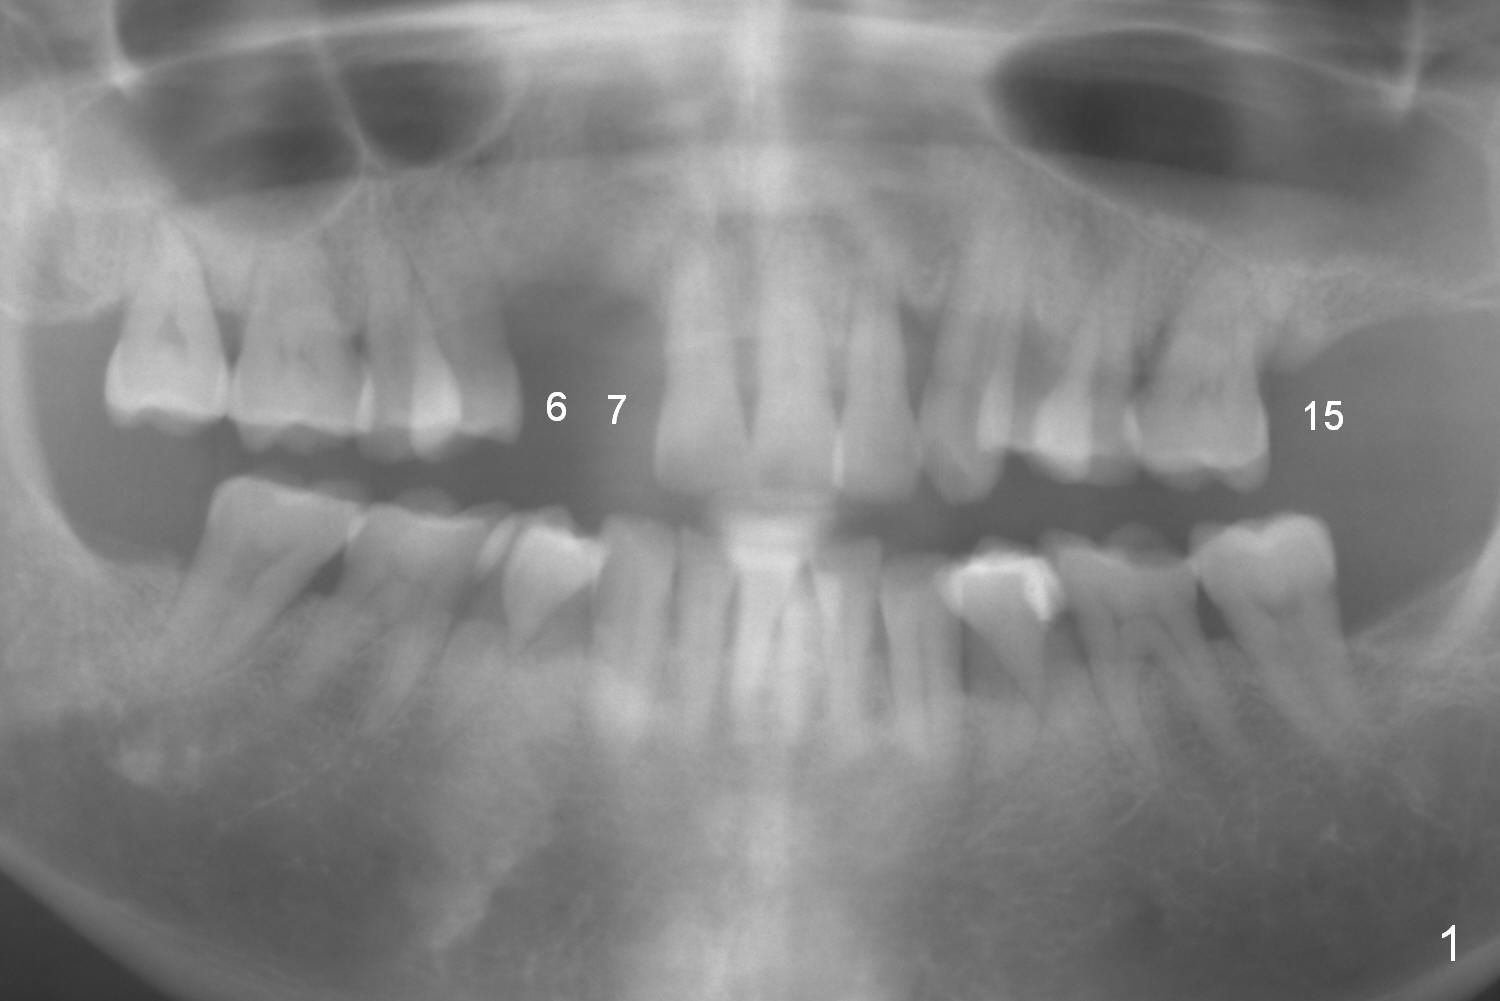

The bone height at #15 is unfavorable (Fig.4). Use 1.6 mm drill for 6 mm to start osteotomy, followed by Magic Expanders (BEB). Since the restorative height is limited due to long-standing edentulism with the supraerupted opposing tooth (Fig.5), consider using Magicore (blue). Use the bone condenser with stopper from Sinus Master kit for sinus lift. Place bone graft distally (red circles), followed by resorbable and nonresorbable collagen membranes (green curved line).